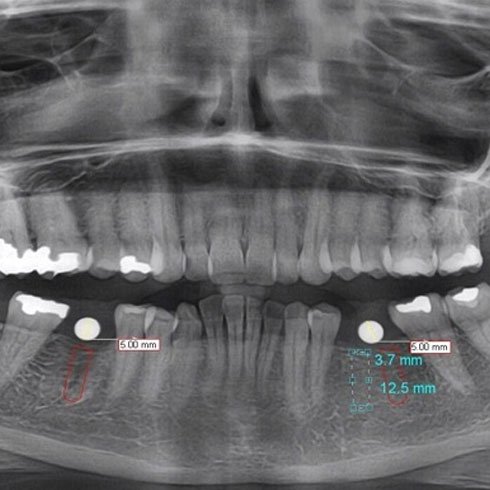

Digital OPG